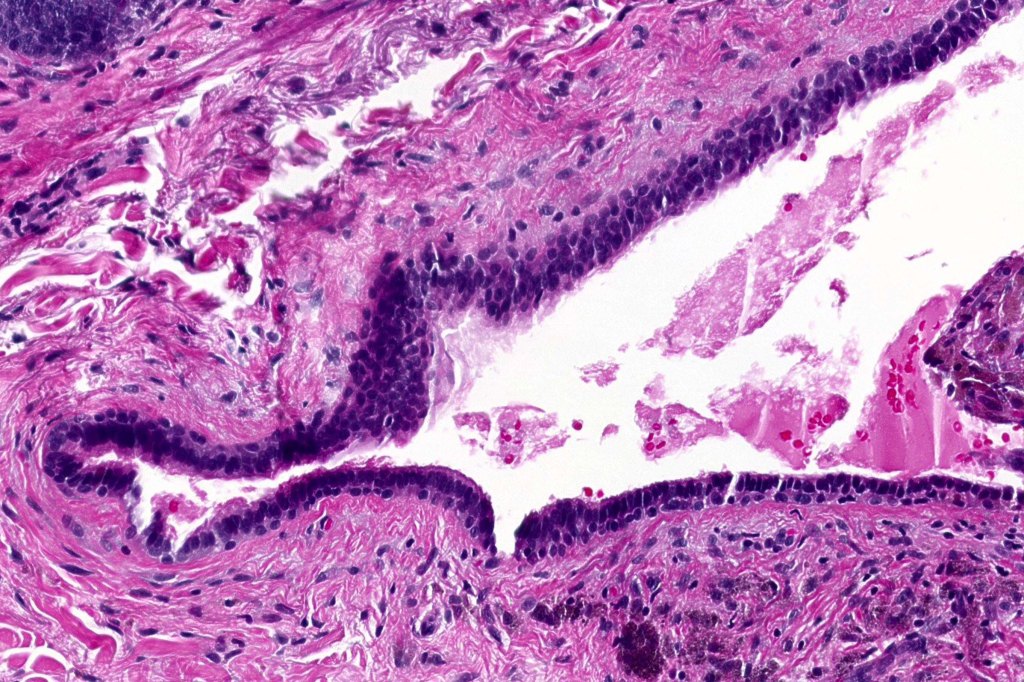

Histological features

•Pseudo-encapsulated unilocular or multilocular

•Outer myoepithelial cells & inner layer of columnar cells with eosinophilic cytoplasm showing decapitation secretion

•Adenomatous/papillary component (cystadenoma)